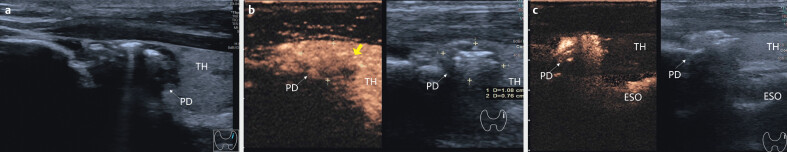

Abstract Image